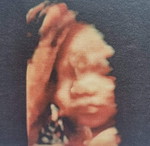

กำลังจะมีลูก